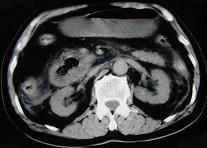

问题 男,78岁,阵发性上腹部疼痛10年伴呕吐,加重1年,影像检查如下图,应诊断为 ( )

选项 A.十二指肠癌 B.十二指肠憩室 C.十二指肠淋巴瘤 D.十二指肠结核 E.肠系膜上动脉压迫综合征

答案 B